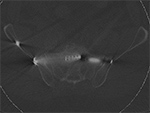

Figure 1 A Figure 1B Figure 2A Figure 2B

Streak artifact Streak artifact Hardware attenuation Hardware attenuation

Streak and Shadow Artifact. (A) Axial CT image of the lumbar spine demonstrates extensive high attenuation linear streak and splay artifact secondary to posterior spinal fusion hardware.  (B) Axial CT image of the left hip demonstrates linear low attention shadow artifact propagating along the axis of greatest metal cross-section, which obscures the femoral neck.